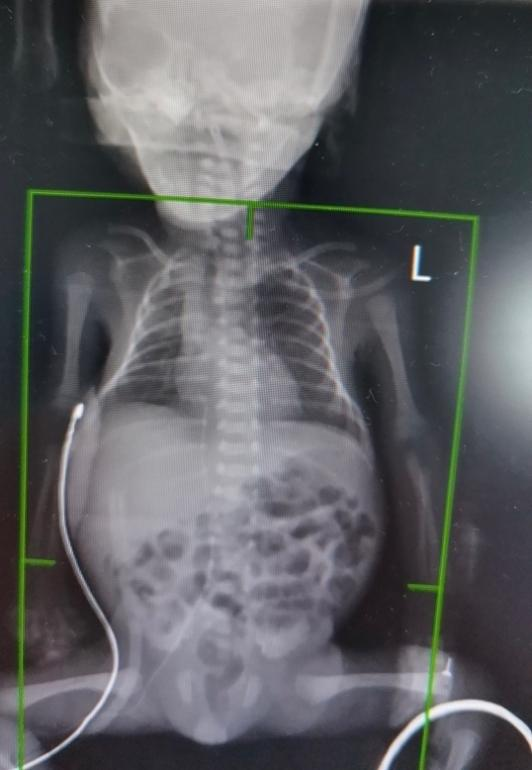

10 月 1 日,在举国同庆的日子里,交大一附院小儿外科团队联合新生儿团队及麻醉手术部团队,成功抢救了从榆林医院千里转运的突发肠穿孔超低体重早产宝宝。宝宝于 9 月 25 日在交大一附院榆林医院剖宫产出生,孕周 28 周,出生体重仅 840 克,为超低出生体重早产儿。

宝宝自出生后不能正常排便,检查发现空腔脏器穿孔。消化道一旦发生穿孔,胃肠道内的气体、消化液、粪便就会进入腹腔,造成腹腔内压力升高、导致呼吸窘迫,还会引起感染、败血症、休克和多器官衰竭。

交大一附院榆林医院新生儿科刘增芳主任联系总院儿科周熙惠主任后,决定立即转运到总院。超低体重宝宝皮肤像胶冻一样半透明,胳膊仅有成人手指般粗细,手术难度大,麻醉风险高。新生儿病区周熙惠、小儿外科曹振杰、麻醉手术部刘学宁多学科专家为患儿紧急施行了剖腹探查术。术中发现宝宝肠道存在梅克尔憩室粘连,并发肠管梗阻、破裂穿孔,小儿外科曹振杰主任遂行肠切除及肠吻合术,超低体重宝宝肠管只有一根吸管粗细,肠吻合采用超细缝线,缝合技术要比绣花还细致。

麻醉医生全程处于紧张状态,术中既要严密监测患儿生命体征,还要密切观察呼吸机通气参数变化,保证氧合参数与血流动力学稳定,在团队 2 个多小时默契配合下,早产宝宝成功脱离生命危险。